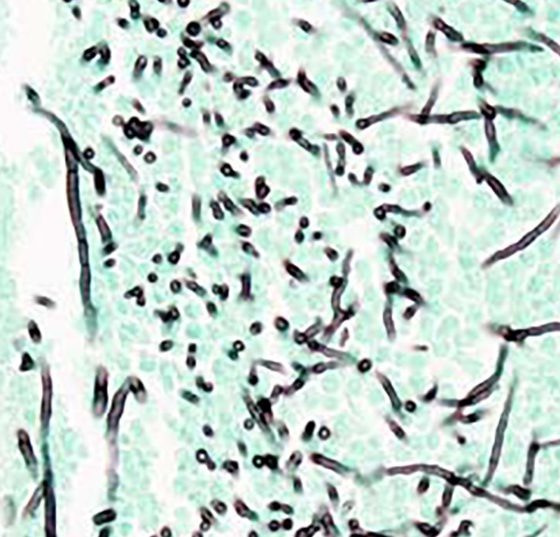

aspergillose_wikimedia

• Antiinfektiva

COVID-19 assoziierte Aspergillose erkennen und adäquat behandeln

Corona hat nicht allein Probleme mit den Atemwegen im Gepäck. Auch eine ­invasive pulmonale Aspergillose kann gehäuft auftreten – in der Regel sehr schnell. Daher ist eine erhöhte Aufmerksamkeit für...…